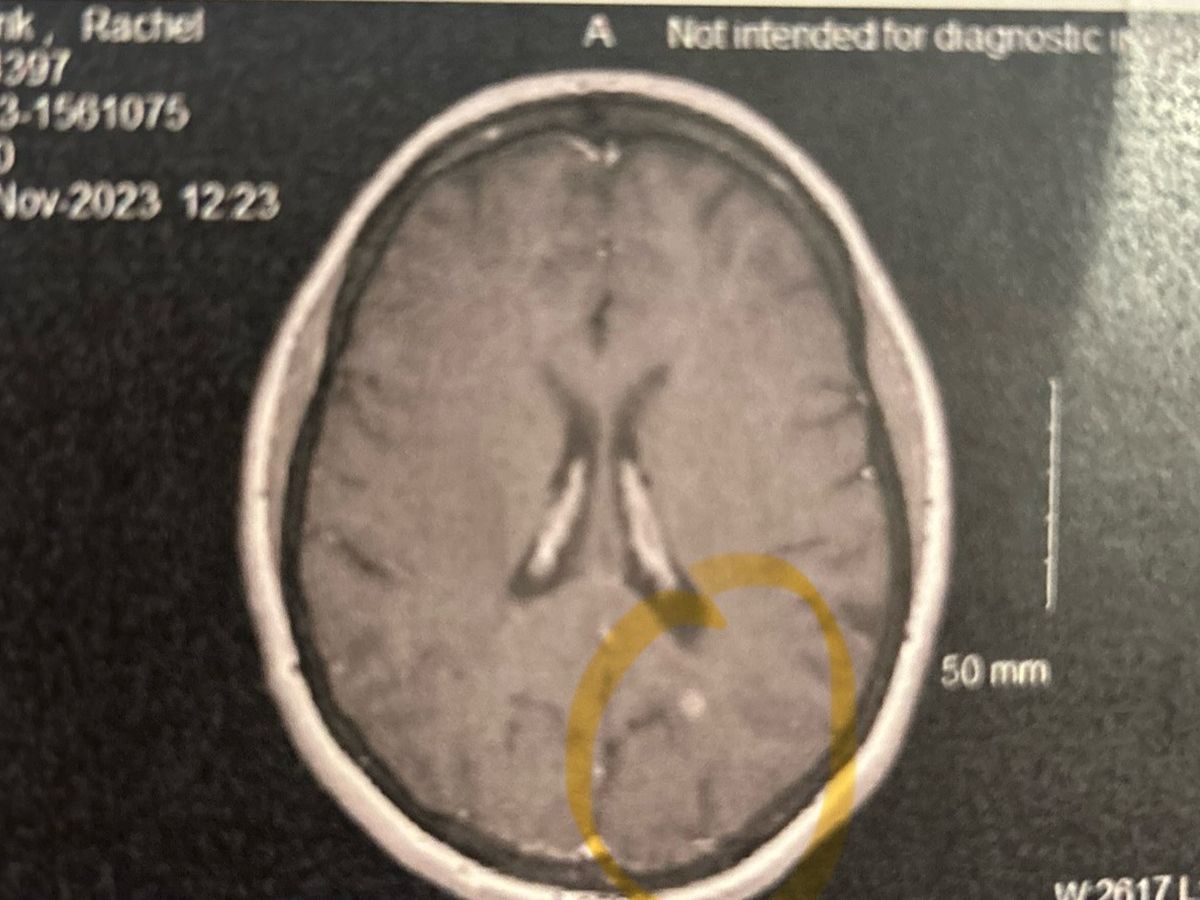

my name is rachel and i’m 30 years old. as most of you know, i’ve been dealing with brain cancer since i was 21. i had a brain surgery to remove the tumor on september 1st, 2015 and it came back as a grade II astrocytoma. i was stable until 2019. my routine MRI’s shown that it had grown back i had another brain surgery on april 9th 2019. i wasn’t so lucky that time and it came back to be a grade III astrocytoma, also known as AA3. they were able to remove 100% of the tumor visible to the human eye but with this type of tumor, it likes to branch out like octopus tentacles and it grasps at other parts of the brain and it almost always returns (hence my recurrence) I did 30 treatments of radiation alongside 42 days of temodar chemotherapy pills and then took one month to heal and then started on 6 additional months of high dose temodar. i was stable again for a little over 4 years. i thought i knocked it out of the park this time around, but i was wrong. in november of 2023 i had another routine MRI and the doctors has told me “it’s back, and there’s not only one tumor anymore, there is now 2 of them and surgery is no longer an option” based off where it is located in my brain now. it is extremely close to the motor strip as well and the corpus callum so they said i would definitely come out with some type of deficit such as blindness or i would lose the ability to walk, talk or drive. i have a 7 year old very active little boy, so i told them “you’re not doing anything to me that could cause me to come out differently than when i came in so whatever you have to do let’s do it” my neuro-oncologist talked with a new radiation doctor and that doctor had talked to the team of folks who did my proton therapy in 2019, and together it was decided the best course of action right now is to have another course of radiation followed by even higher doses of temodar so we can attack it aggressively. about 3 weeks ago, i received a phone call saying the doctors at UC were confident they could do a needle biopsy so we could at least know what we are dealing with. my tumor could still be a grade 3, but it could have gotten worse and turned to a 4, or GBM. GBM is the deadliest form of brain cancer and it has an average of 12-18 months for surviving once you are diagnosed. granted i haven’t had GBM, ive still been dealing with cancer for the last 9 years so it doesn’t seem very promising for me right now. i was told i have about 2 years left but i am determined to prove the doctors wrong and show them cancer picked the wrong person. as far as treatment goes, the option to go with proton radiation was a no brainer. proton therapy is very precise and doesn’t damage surrounding healthy brain matter and given i’m only 30, that is what we are going for again so we don’t cause even more brain damage. since it is my second time getting it, the side effects are higher. seizures are very common in those who have to get radiation to the same area of the brain. but i know i need to get this done so i can survive and be here as long as i can for my son. there are less than 40 proton treatment centers in the entire united states and we are fortunate enough that there is one in west chester ohio. it is still 80 miles round trip, 5 days a week, it will take about 3 hours out of the day with driving and waiting and getting the radiation. 80 miles a day isn’t a walk in the park when the price of gas fluctuates so much. i also am not allowed to drive myself because it makes you fatigued so parts of this is going to go towards gas for whomever takes me up there. i was also advised to not work while all of this is going on because the high dose chemo will keep me pretty sick constantly and the radiation will have me too tired. i have worked since i was 16, so all of this is new to me. i’m not used to asking for help or seeming like i can’t handle things on my own but right now i need help. being a single mom during all of this makes it so much heavier. weston was only 3 the first time i went through this, now he’s 7 and he is going to see that something is wrong with me once i start losing my hair or i can’t get out of bed to take him somewhere to play but that is a whole nother battle itself. i am doing this gofund me to try to stay afloat during all of this since i cannot work. the disability i do get is barely enough to get by as is and now without working, i dont know how im going to do it. please find it in your heart to share this or please donate if you can. i would love to get the word out just so i can have support during these hard moments. i know god has got my back and i will come out on the other side of this. thank you for reading.